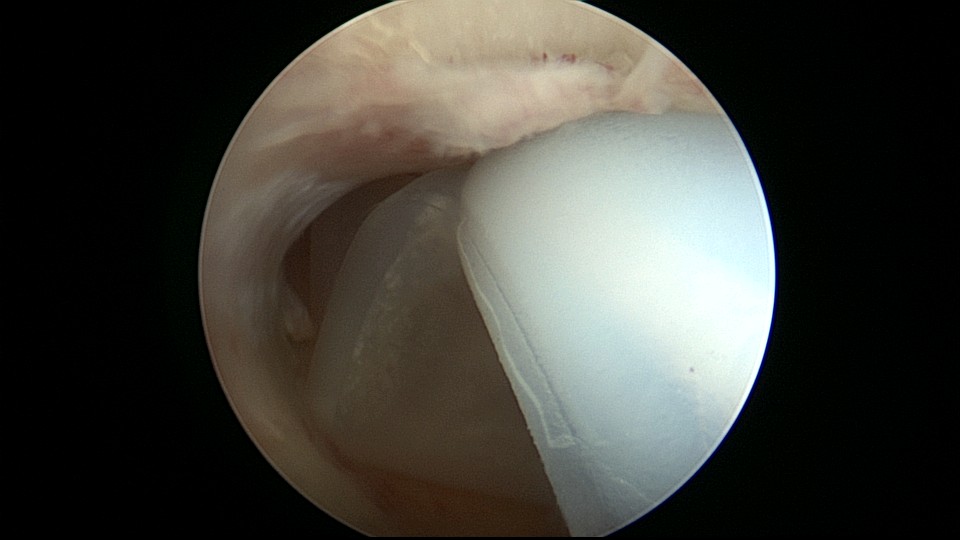

患者21岁,G2P0,两次胎停清宫,月经量减少,眉山某医院B超示宫腔容积小,2021年7月宫腔镜探查,见宫腔两侧、宫底部及左侧宫角粘连,单极电针分粘,恢复宫腔形态,显露双侧输卵管开口。2021年9月宫腔镜二探取球囊,宫腔形态正常,双侧输卵管开口可见。2022年9月自然妊娠12+周,我院建卡,2023年5月孕38+周剖宫产分娩。2025年3月宫腔镜取胚1次,现25岁,G4P1,剖宫产1次。